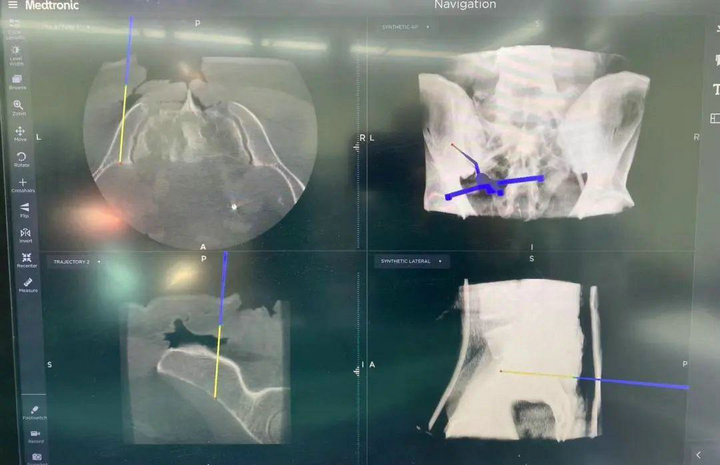

“O”型臂導(dǎo)航系統(tǒng)是一種先進(jìn)的骨科手術(shù)輔助設(shè)備,能精準(zhǔn)定位腫瘤。該系統(tǒng)由“O”型臂術(shù)中影像和手術(shù)導(dǎo)航系統(tǒng)組成,在骨科手術(shù)中發(fā)揮著重要作用,為手術(shù)醫(yī)生實(shí)時(shí)提供術(shù)中三維立體影像,使得手術(shù)醫(yī)生的視角更廣,幫助醫(yī)生避開周圍重要的血管和神經(jīng),精準(zhǔn)定位病變部位和范圍,確保了腫瘤的完整切除和正常骨質(zhì)的最大程度保留,大大提高了手術(shù)的安全性。

精準(zhǔn)切除腫瘤后,借助骨腫瘤科自主研發(fā)的3D打印組合式半側(cè)骶骨假體進(jìn)行重建。并在O臂導(dǎo)航系統(tǒng)的引導(dǎo)下,精確放置假體和螺釘,進(jìn)一步提升患者的重建效果。此外,該系統(tǒng)還可以縮短手術(shù)時(shí)間,加快患者的康復(fù)。

國(guó)內(nèi)首例“O”型臂導(dǎo)航下骶骨腫瘤矢狀位精準(zhǔn)切除